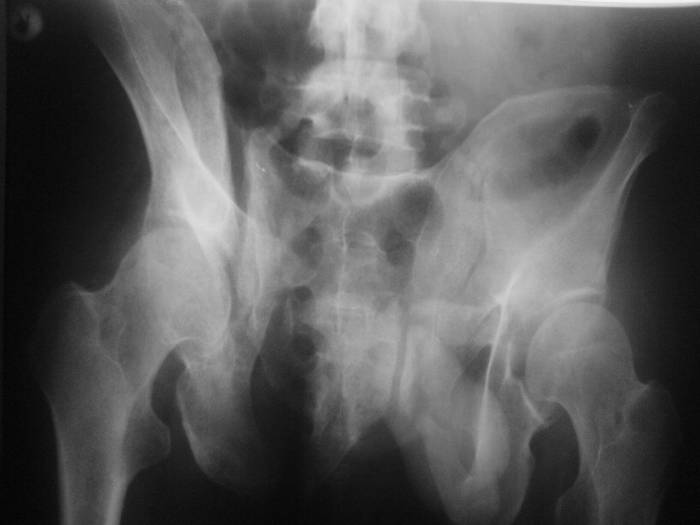

Ситуация такая. Мужчина 50 лет, невысокий, худой. Перелом костей таза

пять месяцев назад. Пришел на костылях. В поисках адекватной помощи в

Имя     : AP1.jpg

Тип     : image/jpeg

Размер  : 30401 байтов

Описание: отсутствует

Url     : http://weborto.net:8080/pipermail/ortho/attachments/20070616/f45c096c/attachment-0003.jpg